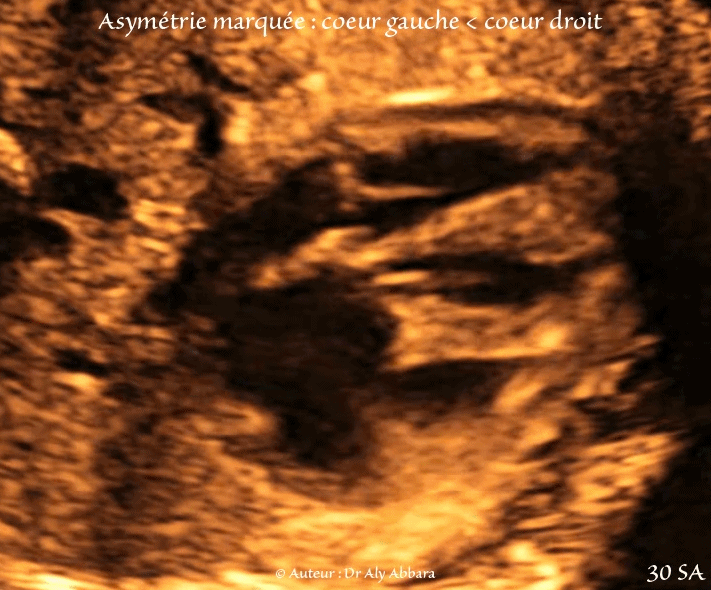

Coupe des quatre cavités cardiaques

Coupe des 4 cavités mettant en évidence la présence d'une asymétrie volumique marquée

► cœur gauche < cœur droit

• Une asymétrie marquée entre le cœur gauche et droit avec :

• diminution du volume du ventricule gauche comparé au ventricule droit ;

• hypoplasie de la valve mitrale avec anneau mitral mesurant 5,7 mm, contre 12 mm pour l'anneau de la valve tricuspide.

• anomalie de l'appareil sous valvulaire mitrale avec un seul pilier mitral visible ;

• diminution du volume de l'oreillette gauche comparé à l'oreillette droite.